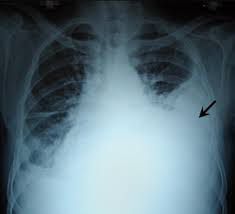

What is hemothorax? Hemothorax is when blood collects between your chest wall and your lungs. This area where blood can pool is known as the pleural cavity. The buildup of the volume of blood in this space can eventually cause your lung to collapse as the blood pushes on the outside of the lung.